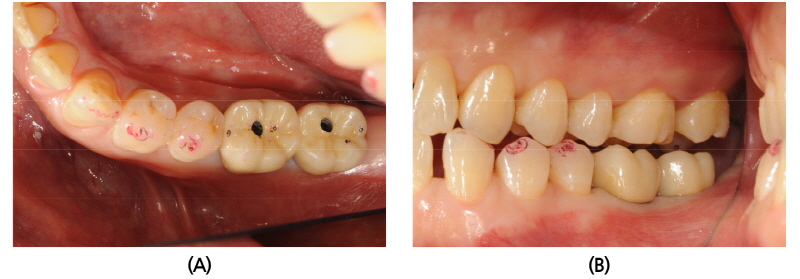

57세 여환이 오랫동안 쓰던 3본 고정성 가공의치가 불편하여 내원하였다. 상악 우측 제2대구치아 접착제 소실로 2차우식이 상당히 진행되어 있었으며, 발치 후 제2소구치는 고정성 가공의치를 자른 후 금관으로 그대로 사용하고, 제1, 2대구치 부위에 임플란트 치료를 하기로 하였다(Fig. 8). 내부 연결형 임플란트(TSIII, Osstem)를 식립하였고, 스캔바디를 이용하여 디지털 인상채득 후 티타늄 맞춤형 지대주, SCRP 전부지르코니아관을 CAD/CAM 제작하였으며, 시착 모형을 3D 프린트 적층 제작하였다. 환자는 재건된 수복물에 만족하였다(Fig. 9).

41세 남환이 어금니가 찬 물, 미지근한 물에 시리다는 주소로 내원하였다. BO inlay 근심과 협측에 잔금이 가 있었고, 치아 파절로 진단을 내리고 발치 후 임플란트(TSIII, Osstem) 식립을 하였다(Fig. 10). 디지털 인상 채득 후 맞춤형 지대주와 전부지르코니아관을 제작하였고, 시착 모형을 3D 프린터로 제작하였다(Fig. 11). 환자는 교합 기능과 심미적으로 모두 만족하였다(Fig. 12).